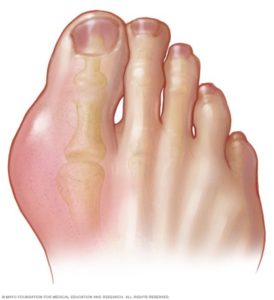

– المفصل المصاب يكون ملتهب – لونه أحمر – تورم مؤلم للغاية لدرجة انه يؤلم عن لمسه

:- أكتر المفاصل المعرضة للاصابة بالترتيب هيا

الاصبع الكبير في القدم لمعظم الحالات –

الكاحل او الكعبين –

احيانا الركبة –